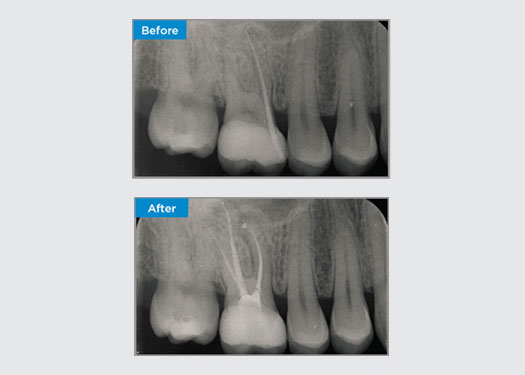

Le patient s’est présenté avec une pulpite irréversible sur la dent 46. Sur la radiographie préopératoire, la dent 46 présente une racine distale supplémentaire (morphologie de la dent Radix Entromolaris). Un balayage CBCT a confirmé la présence d’une racine DL avec une courbure radiculaire sévère. Une sélection minutieuse des limes est essentielle pour cette racine DB délicate.

Dr Jack Lin, Endodontiste, Sydney, NSW Australie

Dans cette situation, la préservation de la structure de la dent/racine est essentielle pour réduire le risque de déviation, de déplacement, de fermeture, de perforation et de fracture de la racine. La sélection des cas, le diagnostic et la planification du traitement préalable sont importants. Le choix de la lime endodontique en fonction de sa flexibilité, de son efficacité et du respect de l’anatomie naturelle de la racine est essentiel.